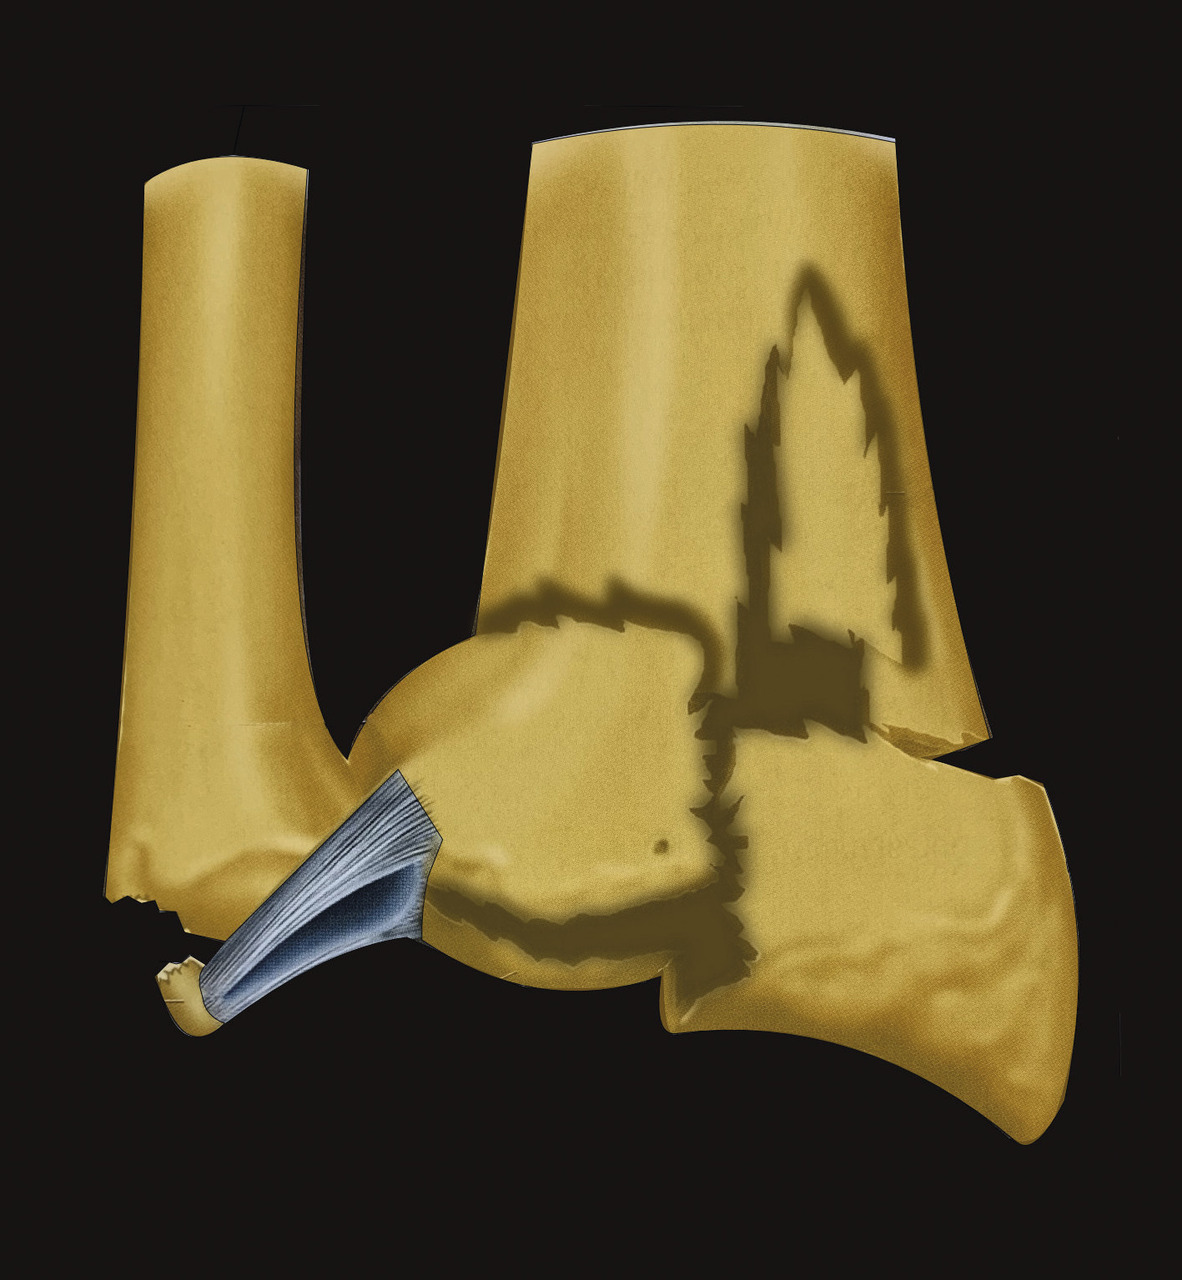

Enfin, le complexe ligament triangulaire prolonge la surface articulaire distale du radius sur son versant médial. Il s’agit d’une structure ligamentaire tendue du versant médial et distal de l’extrémité inférieure du radius, sur le pourtour de l’incisure ulnaire jusqu’à la base de l’apophyse styloïde de l’ulna (fig. 5). Ainsi, l’extrémité distale du radius, l’articulation radio-­ulnaire distale, le complexe ligamentaire triangulaire et l’extrémité distale de l’ulna constituent une entité anatomofonctionnelle continue, composite et indissociable. Les lésions associées aux fractures de l’extrémité inférieure du radius, comme les fractures de la styloïde ulnaire ou les lésions ligamentaires du complexe triangulaire, appartiennent donc au même spectre lésionnel. On s’attachera par conséquent à rechercher systématiquement une participation articulaire aux lésions fracturaires et des lésions ligamentaires associées.